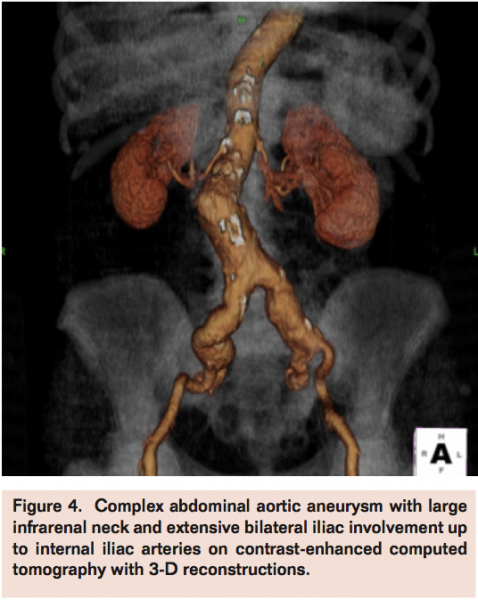

The decrease in open surgery volume for AAA repair in the last decades after the introduction of EVAR is mainly justified by well-demonstrated, consistently lower perioperative risks with new mini-invasive techniques despite the more uncertain durability often requiring reinterventions.9,10 Development of more advanced technologies and devices (fenestrated, branched stent-graft, etc.) progressively expanded the range of suitability for endovascular approaches also in the presence of more challenging and adverse AAA anatomies, such as large and angulated necks, small iliac arteries, and extensive aneurysms. Nevertheless, morphology is still the main and probably irreversible reason of concern for EVAR. Forced application of EVAR when not suited for AAA morphology (Figures 1-4) produces increased failure and complication rates. Schanzer et al reviewed outcomes of 10,228 EVAR performed in a 5-year period in the U.S. and found that only 42% of patients had an anatomy that met the most conservative definition of device instructions for use. The 5-year post-EVAR rate of AAA sac enlargement was exceptionally high at 41%. Notably, the rate of AAA sac enlargement was significantly higher in patients who underwent EVAR outside the instructions for use.11 Therefore, despite the feasibility in deployment, long-term efficacy of EVAR in forced AAA anatomies remains a main drawback allowing these cases to be better pursued by an open surgical approach.

Costin et al published their open AAA practice following the institution of an EVAR program in 2006.5 Authors compared 301 patients (group 1), who underwent open repair before, with 305 patients (group 2) who underwent open repair after the beginning of the stent-graft program experience. They found a significant increase in number of repairs requiring suprarenal clamping, from 6% in the pre-EVAR period to 20% in the initial post-EVAR period. Furthermore, there was higher iliac complexity in the second period: iliac aneurysms were present in 25% of group 1 patients and 42% of group 2 patients (P<.05). The incidence of associated iliac occlusive disease was 12% in group 1 and 20% in group 2 (P<.05).

More recently, Hiromatsu et al compared their perioperative data with open AAA surgery before (n=99) and after (n=125) the EVAR era.13 In the post-EVAR period, the authors found greater need for suprarenal clamping (11.2% vs 3%), a higher proportion of octogenarians (23.2% vs 11.1%), and extensive iliac involvement (35.2% vs 22.2%).13

Thereby, open aneurysm repairs are currently performed primarily in patients with more extensive aneurysms or who are not anatomically suitable for EVAR with the main limitation being an anatomically unfit proximal neck (short, large, thrombosed, angulated) or in patients with EVAR failure (eg, conversion after stent-graft migration, persisting endoleak with aneurysm growth, stent-graft rupture, etc.). Severe vessel calcification, iliac access obstruction, extensive iliac aneurysm extension, and previous aortic graft infection are other common findings in AAAs mainly reserved today for open surgery. These anatomical changes may also pose higher technical challenges for open surgery, such as raised frequency of suprarenal clamping or visceral revascularization and increases in operative duration, use of blood products, intensive care unit stay, hospital length stay, and overall complication rates when compared to repairs in more straightforward and infrarenal AAA, now routinely treated by EVAR.